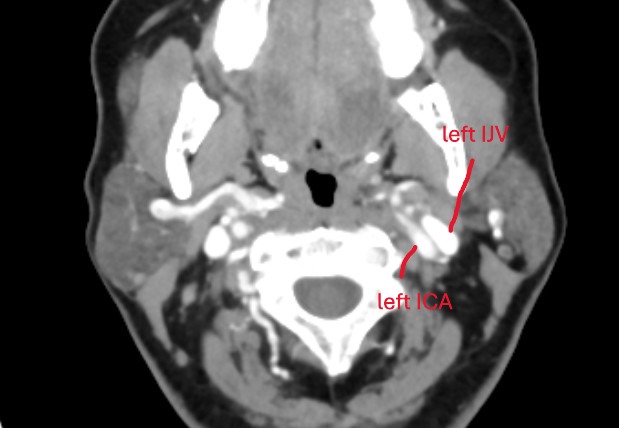

@chrEagle see attached annoted images (5 here of the axial view, and a 3D model in a following post)

Between the skull-base and C1, your left styloid comes in contact with your left IJV. Contact is normal, compression is not. I would be surprised if this contact is causing any symptoms.

Further down, at the level of C1, there is some compression of your left IJV against C1. Neither styloids are contributing to any compression here.

At the level of C2ish, your left IJV becomes compressed by your left ICA. Your ICAs are tortuous, in that they move from an anterior to posterior position and then go back to anterior position. On it’s way to to the posterior position, the left ICA compresses your left IJV.

There is no other IJV compression anywhere.

@chrEagle those are logical explanations I think! The compression by your digastric looks worse on the left (seen in image #3). Where I have labelled your left ICA and left IJV, the IJV is pancaked between the left ICA and the posterior digastric. The posterior digastric touches the right IJV as well, but compression is not as bad. I think it moreso has to do with your left ICA pushing your left IJV into the digastric. Because on the right side you don’t see compression by digastric, but you also don’t see compression by the ICA. So I think the tortuous left ICA is a pretty significant culprit here.